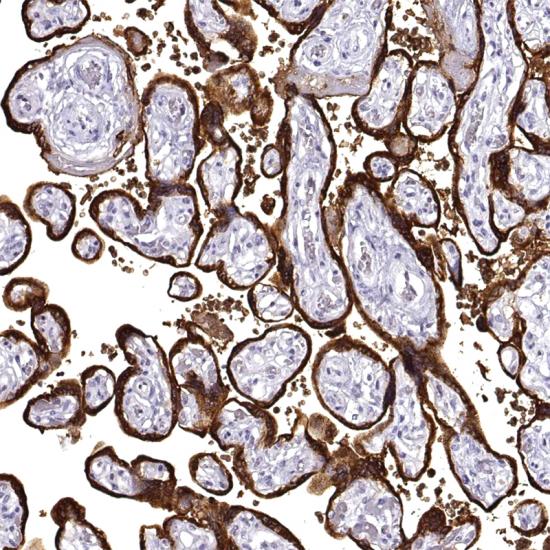

Human Placental Lactogen抗體試劑(免疫組織化學) 閩廈械備20180229號

• 陽性部位:

• 陽性對照:

Human Placental Lactogen是存在于人正常胎盤的一種蛋白。在正常的胎盤、葡萄胎和滋養(yǎng)層及非滋養(yǎng)層的腫物,其染色方式與HCG相似,中間的滋養(yǎng)層細胞優(yōu)勢表達HPL,只有局部表達HCG。主要用于胎盤原位滋養(yǎng)細胞瘤及絨癌的鑒別。